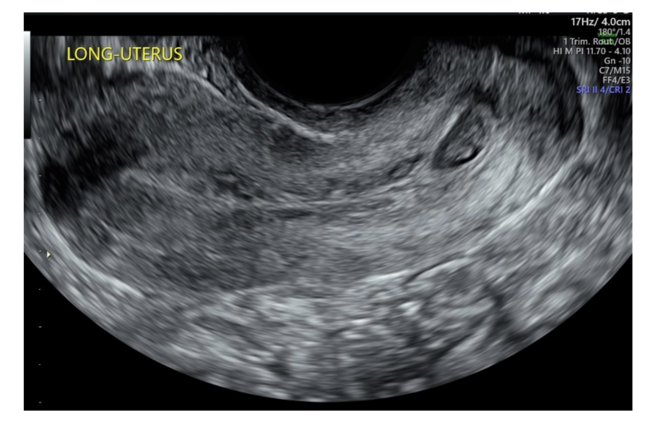

The procedure was performed in the operating room. Initially, the patient was placed supine and bilateral femoral arterial access was obtained with placement of 6F sheaths. A 5F Cobra 2 catheter was used to cross the aortic bifurcation to the contralateral IIA. The catheters were then exchanged over a regular 0.035" Glidewire for 5.5F Fogarty balloons, positioned in the proximal IIAs. Test inflation of the balloons was performed under fluoroscopy to determine balloon volume required for adequate vessel occlusion (Figure 5 and Figure 6). The balloons were deflated, and catheters and sheaths were well-secured. The patient was then shifted into lithotomy position. Due to the size, the CP was seen protruding through a dilated cervix. Uterine vacuum aspiration was subsequently performed by the gynecology team. Following evacuation, the balloons were deflated, and no further bleeding was noted on physical inspection. Total estimated blood loss for the combined procedure was 32 mL. The patient was monitored in recovery for 4 hours postprocedure (as bilateral groin hemostasis was achieved by manual compression and no closure device was used). She was discharged home the same day. On postprocedural telephone follow-up after 2 days, the patient reported some cramping and bleeding and passage of a small amount of clot that was decreasing overall. She otherwise felt well.